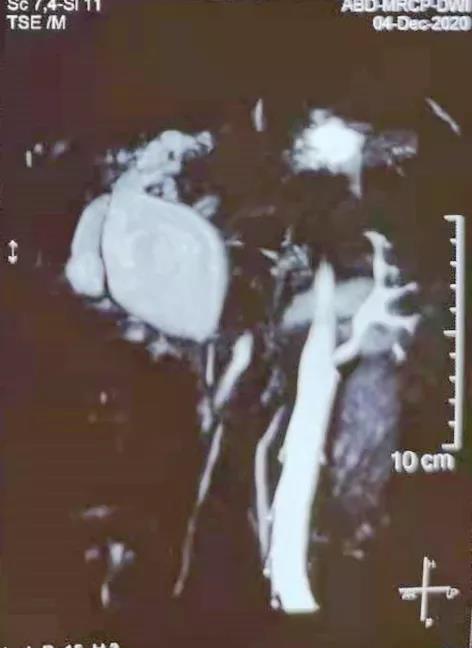

(▲术前MRCP影像资料)

患者女性,38岁,因“间歇性上腹部疼痛半年余”为主诉入住普外科。入院后,科室主任张永全立即召集全科医师对患者进行详细检查,并对病情进行了分析讨论,最终诊断为:胆总管囊肿(Ⅰ型)。手术指征明确,在得到患者及家属同意后,由张永全主任主刀,李金科副主任医师、韩云英主治医师、崔仁杰住院医师协助,在全麻下为患者行先天性胆总管囊肿切除胆道重建成形术,术中完全切除胆总管囊肿及开口于囊肿的胆囊,行肝总管空肠Roux-Y吻合术,并留置胆道支架管,手术过程顺利,患者术后安返病房,恢复良好。